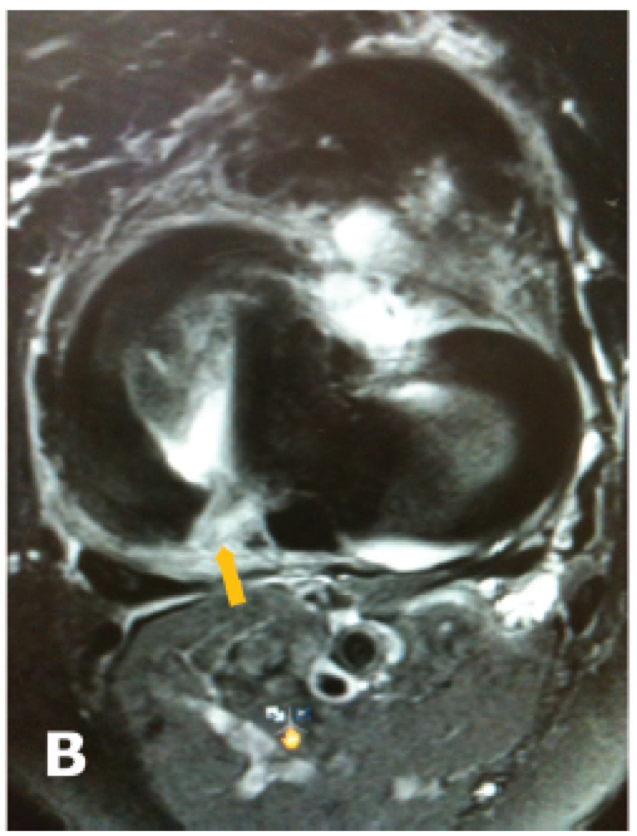

MRI

Findings

- meniscal extrusion

- meniscal ghost sign on sagittal (missing meniscus)